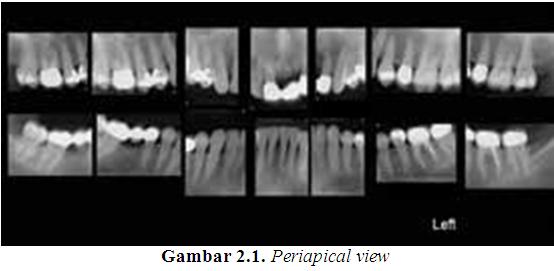

Periapical view

Periapical view diambil dari keduanya gigi bagian anterior dan posterior. Tujuan dari tipe gambaran ini adalah untuk menangkap ujung akar pada film. Gambaran ini memungkinkan seorang dokter gigi untuk memvisualisasikan gigi begitu juga dengan tulang sekelilingnya secara keseluruhan. Nama periapical berasal dari bahasa Latin “peri”, yang berarti “sekeliling”, dan “apical” yang berarti ujung.